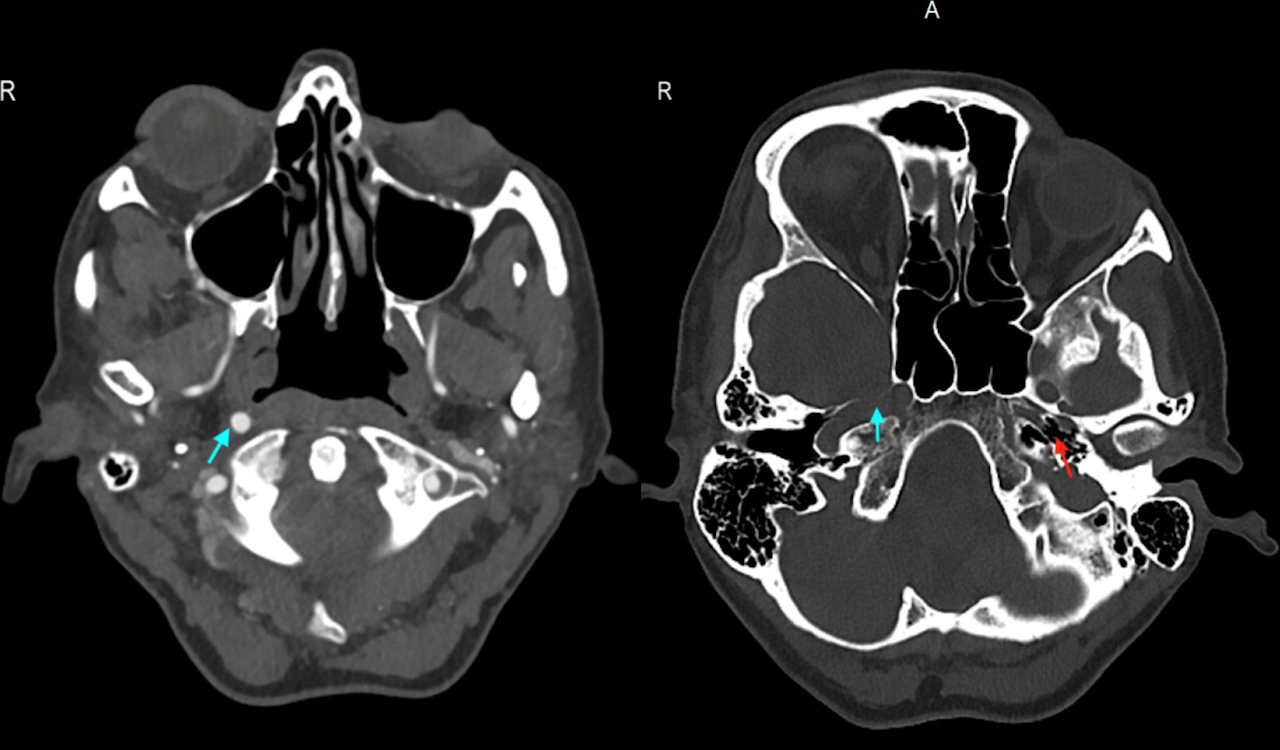

Права сонна артерія та правий канал у кістці жінки були нормально розвинені (блакитні стрілки), ліва внутрішня сонна артерія була відсутньою, а лівий канал — недорозвиненим (червона стрілка). Lai & Ratnayake / BMJ Case Reports, 2025

Але після ангіографії, тобто сканування судин, і повторного перегляду знімків комп’ютерної томографії лікарі виявили, що в пацієнтки від народження не було цієї артерії. На це вказав недорозвинений канал лівої сонної артерії у скроневій кістці. На знімках комп’ютерної томографії в жінки виявили лакунарний інсульт — відмирання нервових клітин у невеликій ділянці в глибинних структурах мозку. Позаяк у пацієнтки не було порушень мозкового кровообігу, попри відсутність внутрішньої сонної артерії, як і факторів ризику інсульту, таких як шкідливі звички та високий рівень холестерину в крові, то причиною інсульту назвали хворобу малих судин невідомого походження.